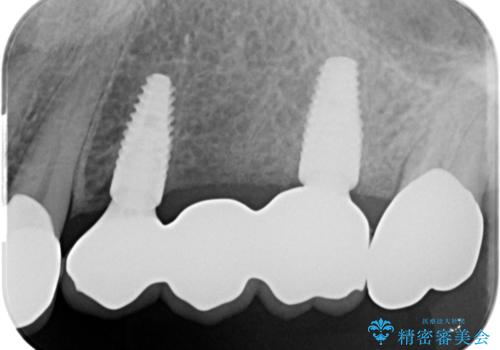

複数の奥歯の欠損 インプラントによる咬合機能回復

- 多数の奥歯を失い、咬合機能の回復を希望され来院されました。

このような場合、入れ歯、もしくはインプラントによる咬合機能の回復のご提案となります。

「より今後しっかり噛めるようになりたい。」というご希望を踏まえて、インプラントによる治療計画を立案します。

- 105.6万円(インプラント×2・チタンカスタムアバットメント×2・ジルコニアクラウン×3・仮歯×3)費用は治療当時の料金となります